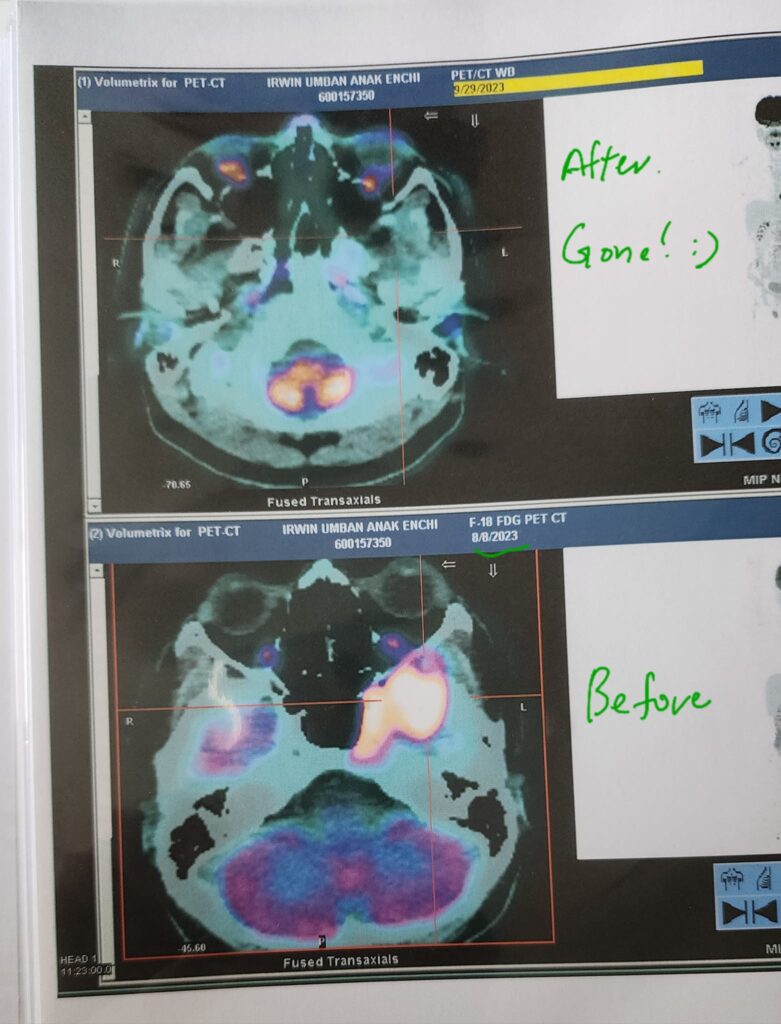

It wasn’t overnight, but I began feeling better — more energy, clearer thinking, and my energy was totally normal. I even went for jogging every morning. Then, in September 2023, I did another PET scan.

It showed no traces of cancer. None at all.

Me and Jean couldn’t believe it. We were grateful but still cautious, afraid it might return. So we kept doing exactly what we’d been doing — combining allopathic, herbal, and lifestyle approaches.

March 2024 – Still Cancer-Free

Six months later, in March 2024, I did another PET scan (results out on 2nd April 2024) . It confirmed what we prayed for: still no cancer detected.